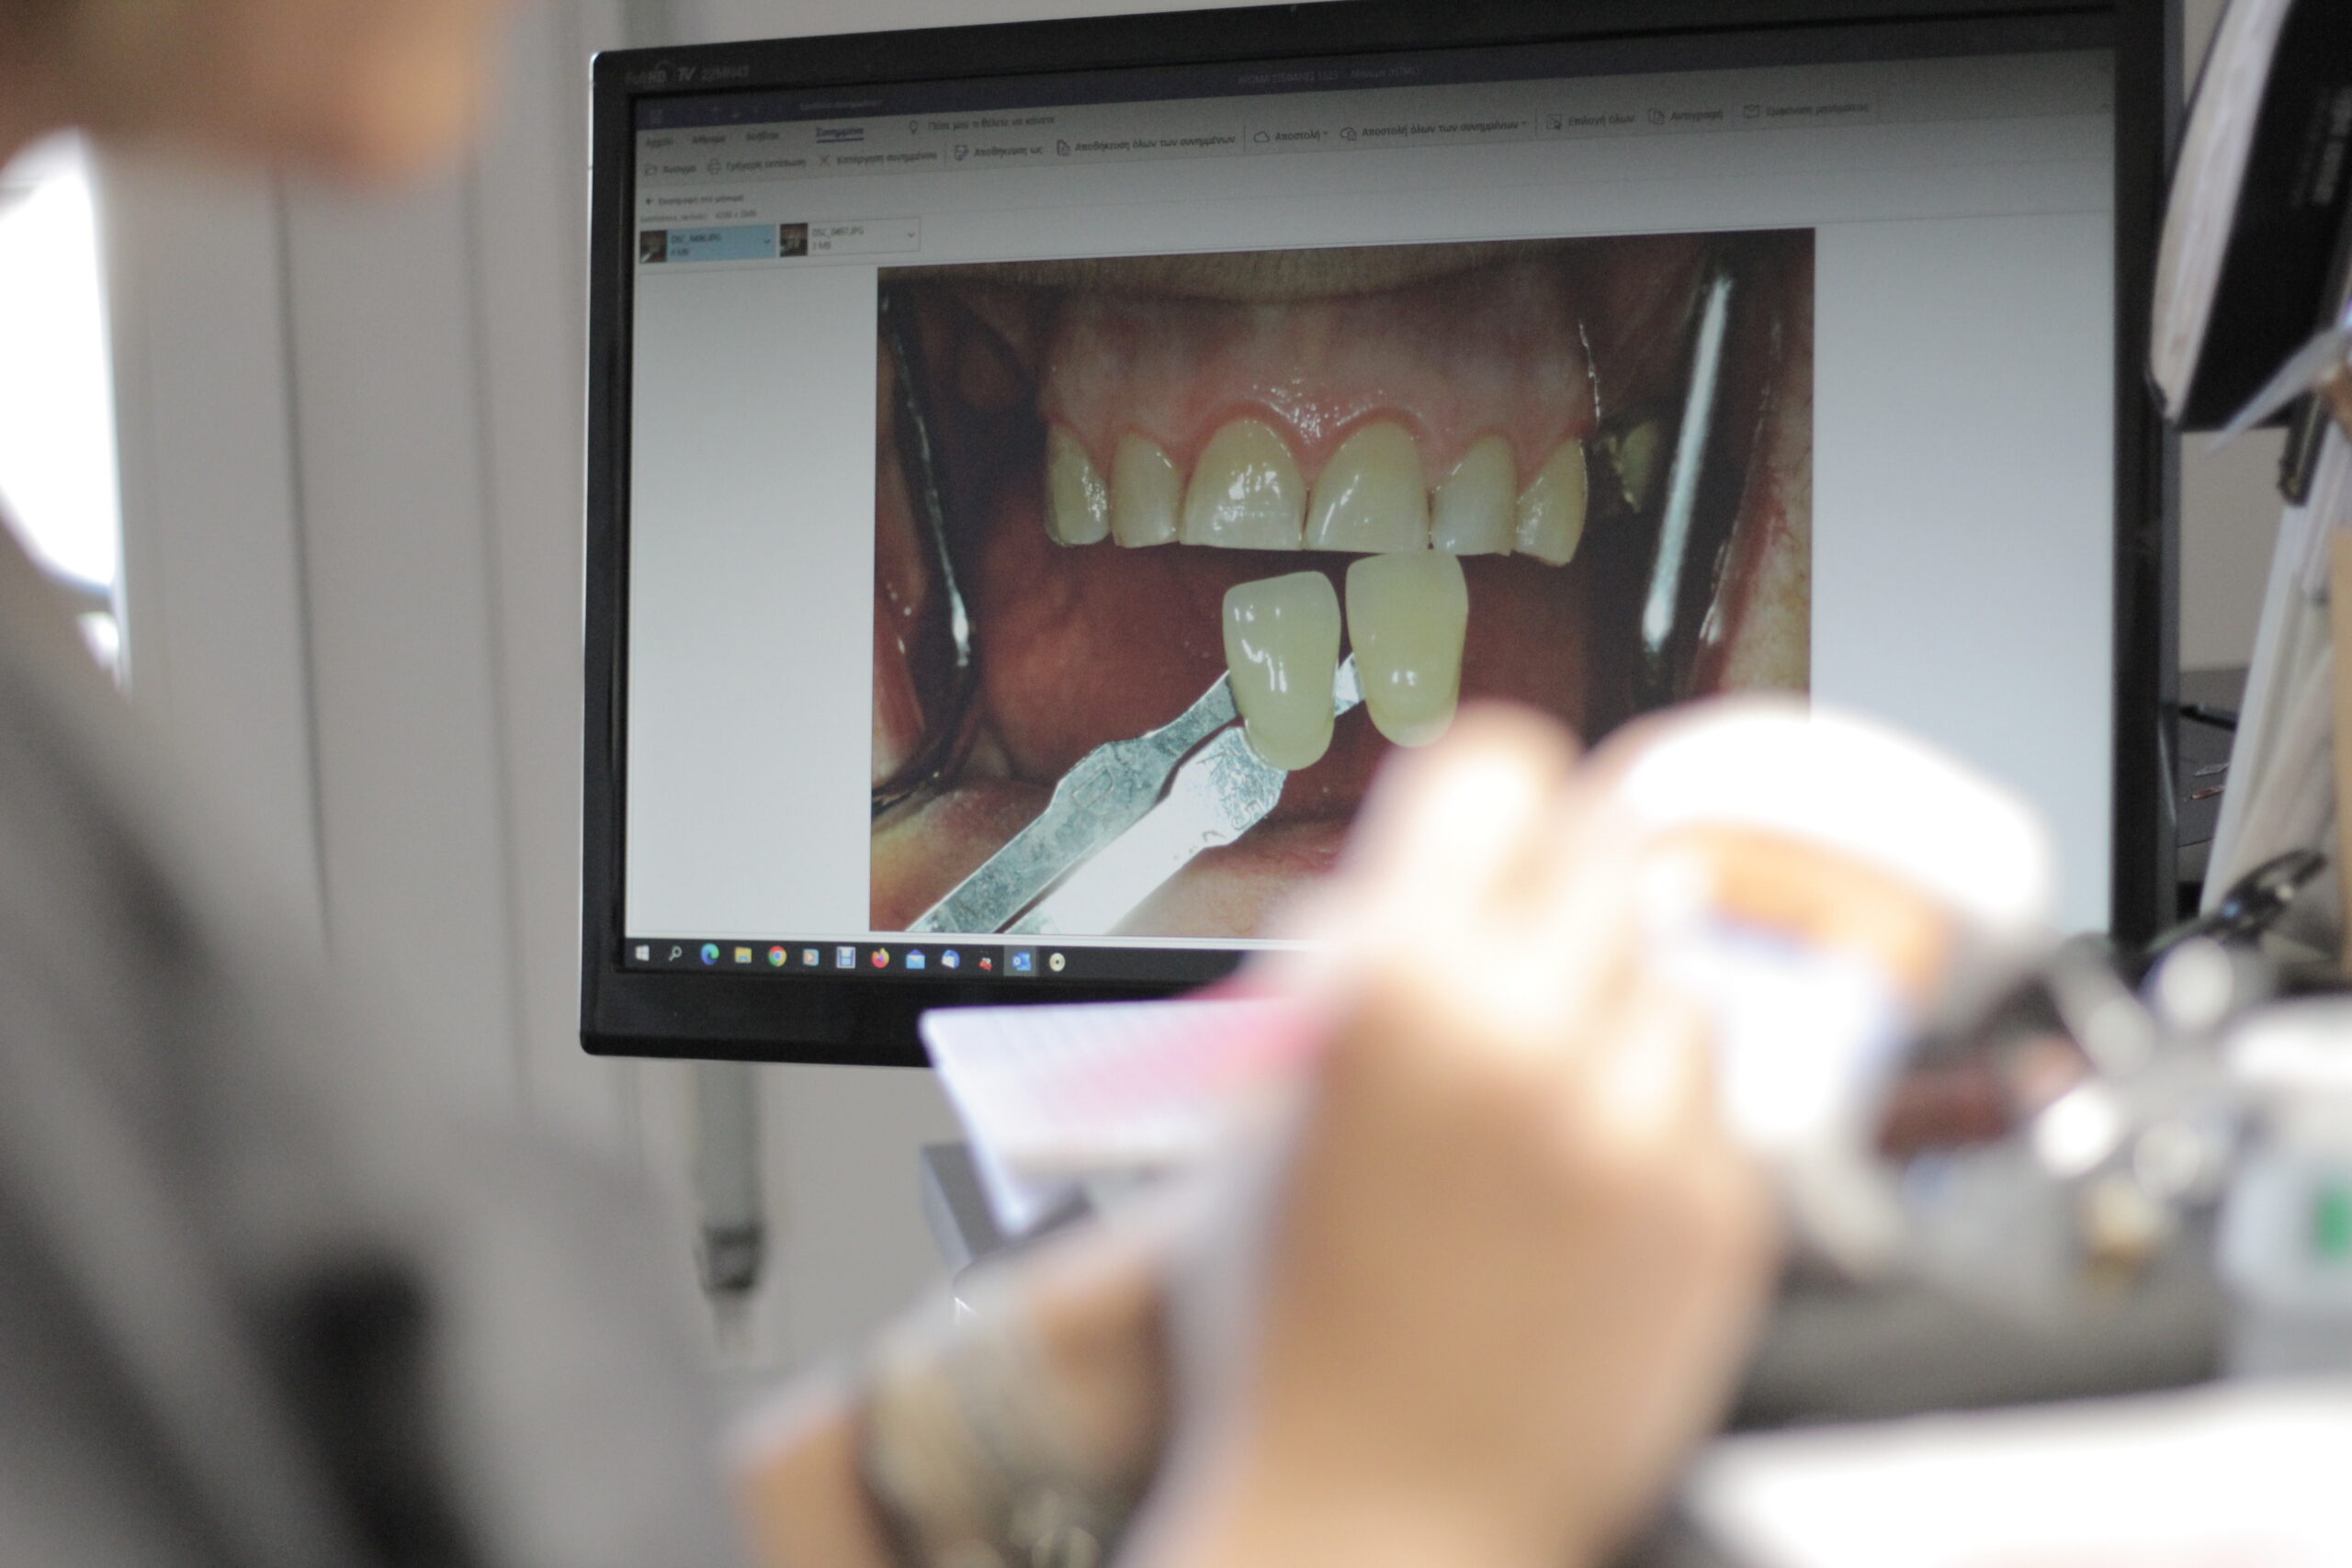

ΠΡΟΣΦΕΡΟΥΜΕ ΠΟΙΚΙΛΙΑ ΟΔΟΝΤΙΚΩΝ ΑΠΟΚΑΤΑΣΤΑΣΕΩΝ ΚΙΝΗΤΗΣ ΚΑΙ ΑΚΙΝΗΤΗΣ ΠΡΟΣΘΕΤΙΚΗΣ

Η Odontolab ειδικεύεται στην προσθετική αποκατάσταση, παρέχοντας στους οδοντιάτρους

εξαιρετικές, προσαρμοσμένες, εξατομικευμένες αποκαταστάσεις για τους ασθενείς τους.

Αυτό μπορεί να χωριστεί σε δύο μεγάλες κατηγορίες.